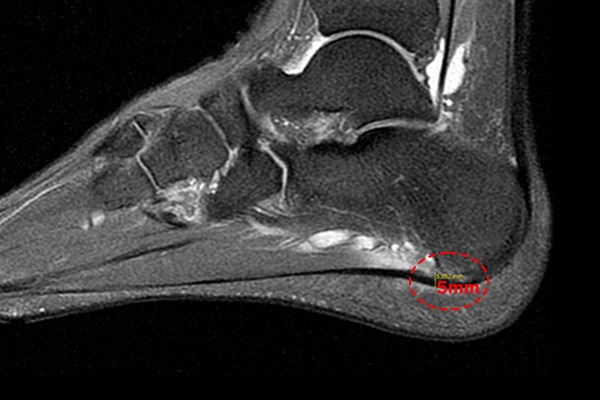

환자분의 발바닥 상태를 자세히 파악하기 위해서 MRI 검사를 진행하였고, MRI에서 까만 족저근막 주위에 하얀 염증이 확인되었고,

96707d45bfa78bc815f4e3f85a28a525_1757924014_36.jpg

발바닥 부착부에도 염증이 확인되어 족저근막염(Plantar fasciitis)을 진단하였습니다.

보통 족저근막의 두께가 4~5mm 이상일 때 수술적 치료를 시행하게 되는데, 환자분의 족저근막 두께는 5mm 정도로 측정되었고, 앞서 2년간 여러 보존적 치료를 시행했음에도 증상이 호전되지 않았기 때문에 환자분께 현재 발바닥 상태와 수술적 치료의 필요성을 설명드렸고, 족저근막 내시경 유리술(Endoscopic plantar fascia release)을 시행하였습니다.